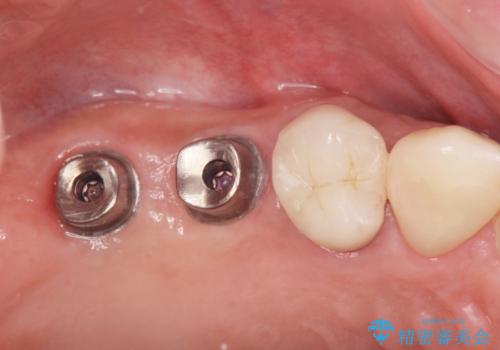

- 歯を抜いたまま放置してしまい、「やはりしっかりと噛めるような状態にしてほしい」とインプラント治療を希望され来院されました。

人工歯根であるインプラントを埋入することで奥歯でまたしっかりと噛める咬合機能を回復します。

- 88万円(インプラント×2・仮歯×2・チタンカスタムアバットメント×2・ジルコニアクラウン×2)費用は治療当時の料金となります